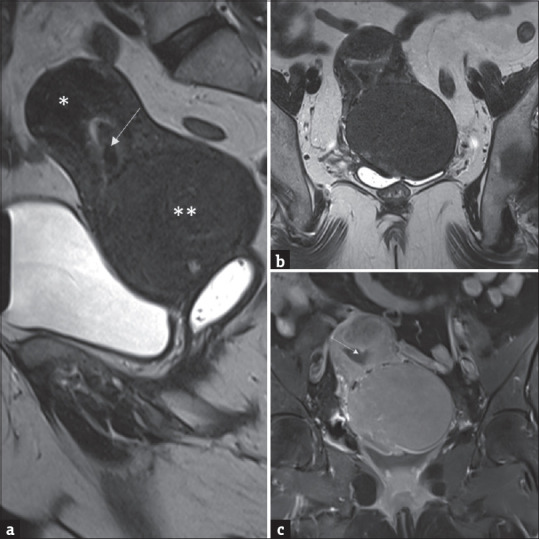

Postmenopausal bleeding is an alarming symptom that needs careful consideration. Endometrial polyps co-existing in the background of endometrial hyperplasia/endometrial cancer is well-established. However, it has been very sparsely reported in the background of atrophic endometrium. The authors report a unique case of concurrent atypical endometrial polyp with cervical intraepithelial neoplasia (CIN) in the background of an atrophic endometrium. A 53-year-old multiparous, postmenopausal lady of Asian ethnicity presented with recurrent episodes of bleeding per vaginum. She did not give any history of exogenous estrogen intake, diabetes, hypertension, or any other surgical risk factors for endometrial malignancy. Her body mass index was 23.9 kg/m2. Magnetic Resonance Imaging revealed a large cervical fibroid, endometrial thickness 8 mm (mixed with blood clots), and focal adenomyosis. Outpatient endometrial sampling was unsatisfactory. She underwent a total hysterectomy with bilateral salpingo-oophorectomy. An incidental hidden diagnosis of concurrent atypical endometrial polyp with CIN underlying the cervical leiomyoma was made. This is the first of its kind to be reported so far. It is not known whether such an association could be due to cervical leiomyoma or de novo.